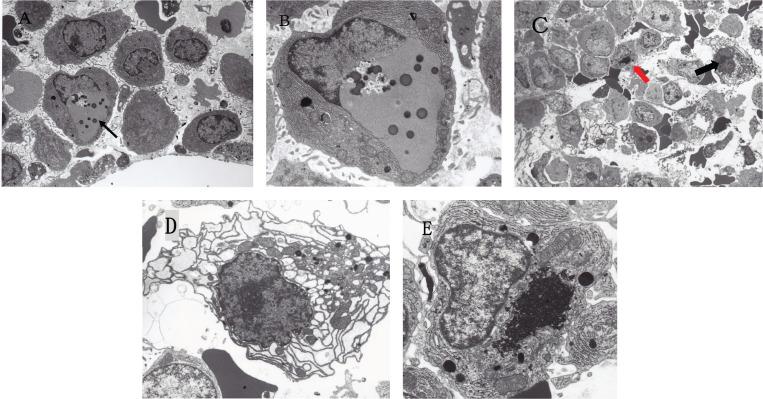

Clarithromycin (CAM), a semisynthetic macrolide antibiotic, is a widely used antibacterial drug. Recently, the efficacy of CAM as an add-on drug for treating multiple myeloma (MM) has been noted. Its effect on treating MM has been confirmed in combination chemotherapies that include CAM. However, a single treatment of CAM has no efficacy for treating MM. Many myeloma growth factors (MGFs) including interleukin (IL)-6 are known to be closely involved in the development of MM. CAM has been shown to suppress many MGFs, particularly IL-6. The possible mechanisms of action of CAM in treating MM have been suggested to include its immunomodulatory effect, autophagy inhibition, reversibility of drug resistance, steroid-sparing/enhancing effect and suppression of MGFs. In addition, MM is characterised by uncontrolled cell growth of monoclonal immunoglobulin (Ig)-producing neoplastic plasma cells. Large quantities of unfolded or misfolded Ig production may trigger considerable endoplasmic reticulum stress. Thus, MM is originally a fragile neoplasm particularly susceptible to autophagy-, proteasome- and histone deacetylase 6-inhibitors. Taken together, CAM plays an important role in MM treatments through its synergistic mechanisms. In addition, CAM with its pleiotropic effects on cytokines including IL-6 and indirect antiviral effects might be worth a try for treating COVID-19.

克拉霉素(CAM)是一种半合成大环内酯类抗生素,是一种广泛使用的抗菌药物。最近,人们注意到CAM作为治疗多发性骨髓瘤(MM)的附加药物的疗效。其在包括CAM的联合化疗中对治疗MM的效果已得到证实。然而,单独使用CAM治疗MM无效。许多骨髓瘤生长因子(MGFs),包括白细胞介素(IL)-6,已知与MM的发展密切相关。已证明CAM可抑制许多MGFs,尤其是IL-6。CAM治疗MM的可能作用机制包括其免疫调节作用、自噬抑制、耐药性逆转、类固醇节省/增强作用以及对MGFs的抑制。此外,MM的特征是产生单克隆免疫球蛋白(Ig)的肿瘤性浆细胞不受控制的细胞生长。大量未折叠或错误折叠的Ig产生可能引发相当大的内质网应激。因此,MM本质上是一种脆弱的肿瘤,特别容易受到自噬、蛋白酶体和组蛋白去乙酰化酶6抑制剂的影响。综上所述,CAM通过其协同机制在MM治疗中发挥重要作用。此外,CAM对包括IL-6在内的细胞因子具有多效性作用以及间接抗病毒作用,可能值得尝试用于治疗COVID-19。